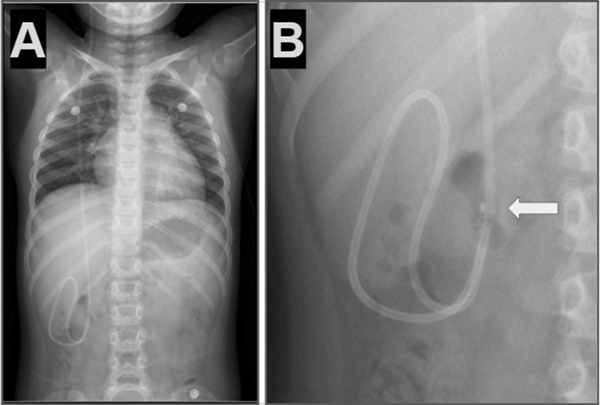

Caso 2. Paciente femenina de 8 años con antecedentes de hidrocefalia congénita y colocación de DVP al mes de vida que presentó cefalea y vómitos. Tomografía de cerebro simple evidenció ventrículos dilatados en comparación con estudios previos. Radiografía de sistema mostró la punta del catéter distal fuera de la cavidad peritoneal (Figura 2).

Figura 2. Caso 2: A) Se observa Rx de tórax y abdomen (frente) con catéter distal a nivel abdominal con migración retrógrada. B) Magnificación de Rx de abdomen que evidencia catéter en doble caño con signo radiológico del “caño de escopeta” o “signo del anzuelo” (flecha blanca) C) Imagen esquemática representando la migración retrógrada de la punta de catéter distal (flecha blanca).

Caso 3. Paciente femenina de 7 años con antecedentes de síndrome de Moebius, hidrocefalia congénita y colocación de DVP al nacer que presentó vómitos e irritabilidad. Tomografía de cerebro simple evidenció dilatación ventricular en comparación con imágenes previas. Radiografía de sistema mostró catéter distal fuera de la cavidad peritoneal (Figura 3).

Figura 3. Caso 3: A) Se observa Rx de tórax y abdomen (frente) con catéter distal a nivel abdominal con migración retrógrada. B) Magnificación de Rx de abdomen que evidenció catéter en doble caño con signo radiológico del “caño de escopeta” o “signo del anzuelo” (flecha blanca) C) Imagen intraoperatoria que muestra la regresión del catéter en disposición paralela con la imagen típica de “doble caño” o “caño de escopeta”.